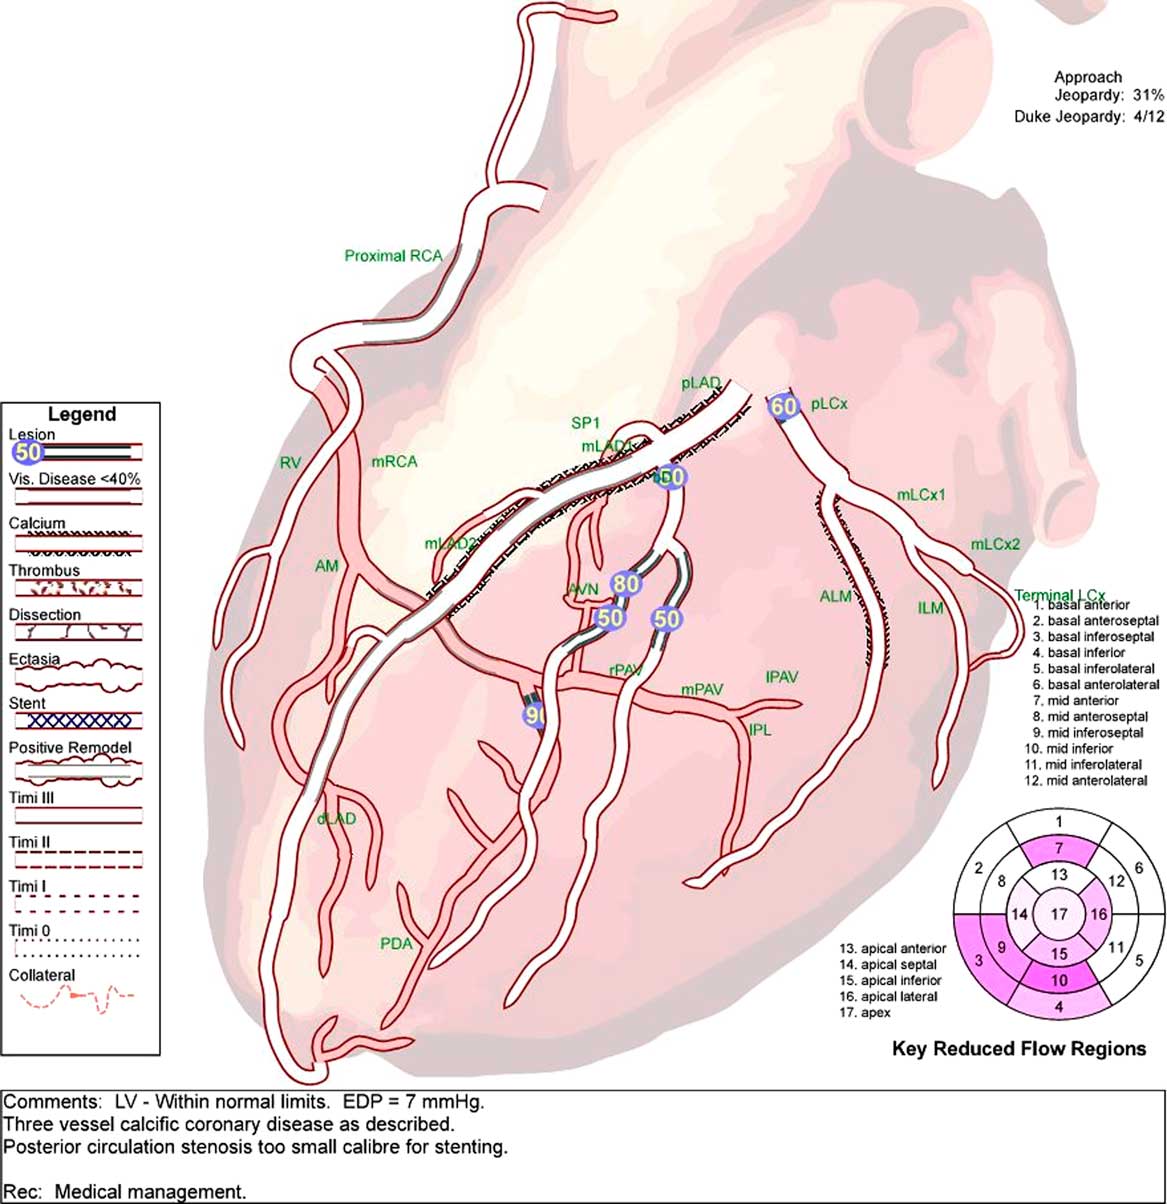

As part of the cardiac workup, an exercise thallium test was performed, whereby the patient exercised for 4 minutes 10 seconds, and demonstrated 2 mm upsloping ST depression infero-laterally with exertional angina. Myocardial perfusion imaging revealed a moderate volume of ischemia in the right coronary artery (RCA) territory. Coronary angiography (Figure 1) revealed a 90% distal posterior circulation stenosis that was felt to be too small for stenting, and non-flow limiting disease elsewhere (60% proximal left circumflex, 50% diagonal, and 80% diagonal branch). Mr. S had an MRI brain and C-spine which demonstrated diffuse smooth dural thickening with enhancement in the brain (Figure 2) prompting a lumbar puncture. This was unremarkable (no opening pressure was performed by interventional radiology under fluoroscopy). CT chest/abdomen/pelvis was negative for sarcoid or a primary neoplasm, but revealed a partially occlusive thrombus of the inferior mesenteric vein. The dural enhancement shown on MRI was felt to be due to extramedullary hematopoiesis, which has been reported to occur in polycythemia.Reference Ito, Fujita and Hosogane 4 Detailed investigations including immunoglobulin G (IgG) subclasses and clinical follow-up have not shown evidence of other causes for the MRI findings. Per hematology, Mr. S was started on lifelong anticoagulation (Warfarin) in hospital given the inferior mesenteric vein thrombus.

Figure 1 Cardiac angiogram demonstrating multivessel calcific coronary disease, most prominently 90% stenosis in the posterior circulation that was too small for stenting. Medical management advised.